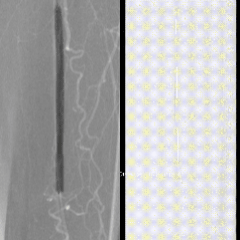

图:Eluvia药涂支架(6-120mm)